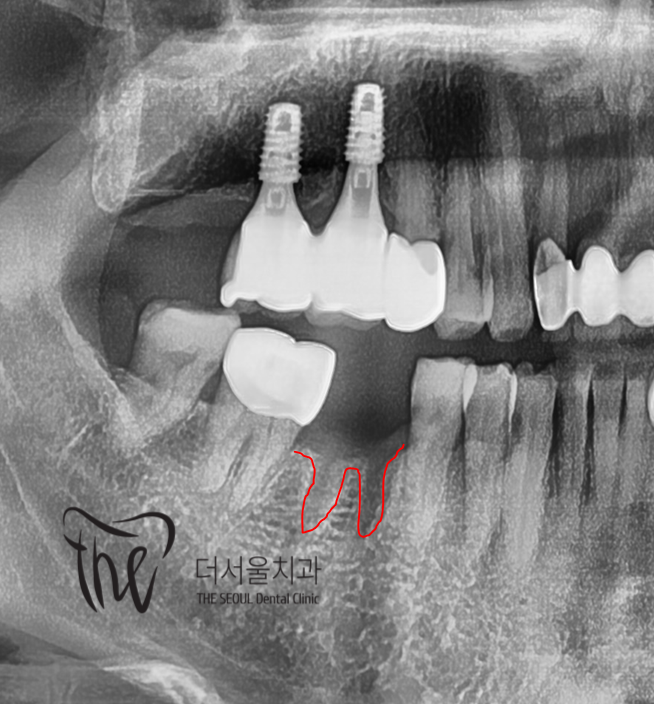

그렇게, 발치가 되면은 그대로 두는게 아니라

최대한 빠른 시일내에 임플란트 시술 판단을

내려야 됩니다.

맞물리고 있는 대합치가 아래로 내려오는,

정출 현상이 일어난다던지 또는 인접치들이

이동이 되면서 앞쪽으로 쓰러질 수 있기 때문에

결국 더 큰 문제들을 초래 할 수 있게 됩니다.

그래서, 이럴 때는 디지털 임플란트 진단 방식을

쓰면 한결 편하면서 더 빠르게 진단을 내릴 수

있게 됩니다.

일단, 치아 사이 충치 가 있었던 곳에는

크라운 치료 및 보철 치료로 대체를 해드리면 되고